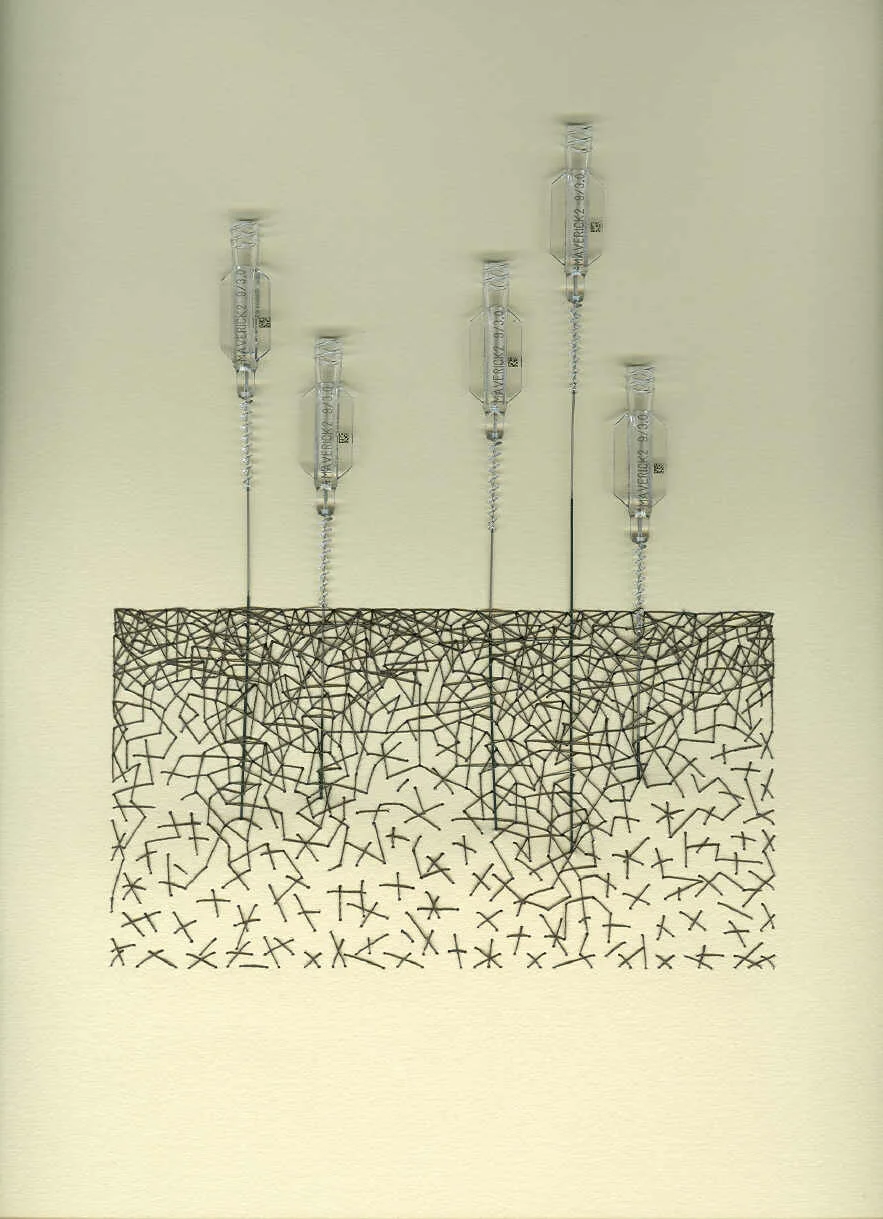

I’ve also had the pleasure of creating artwork for another corporate headquarter building based in MN. Boston Scientific commissioned me to create found object works that featured products which they created. You’ll see below some of those that feature angioplasty ports and balloons.

Chaos 1